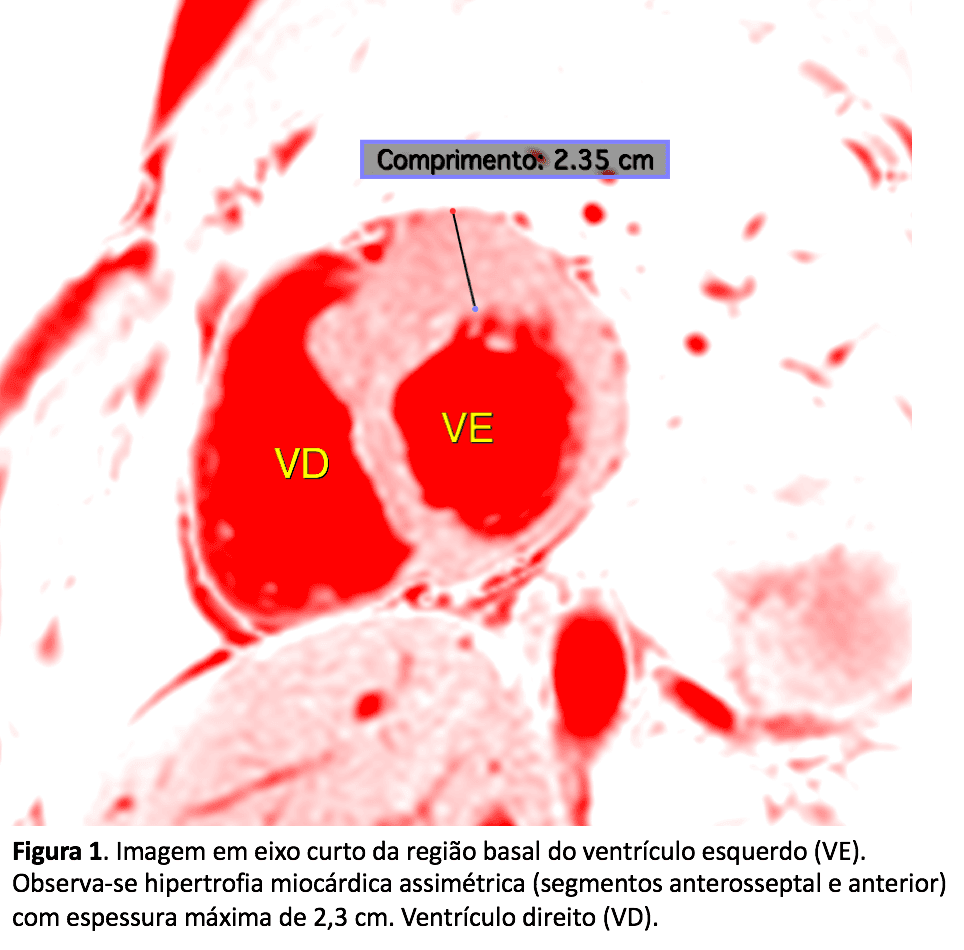

A miocardiopatia hipertrófica é uma doença genética caracterizada pela hipertrofia do músculo do coração. Pode atingir qualquer área do órgão, sendo o mais comum acometer a região do septo interventri…